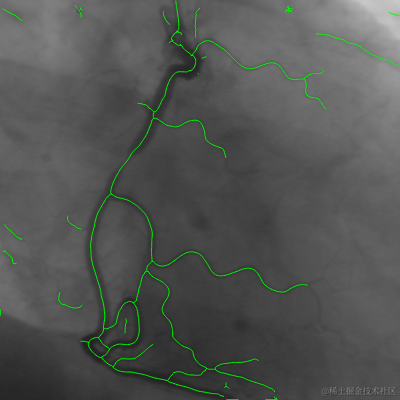

lines_gauss和edges_sub_pix 输出的XLD的区别对比如下:

相信大家已经看出了两者的区别了。

图像的“边缘”指的是:图像中灰度有明显跳变的地方。如果在图中画一条“有一定宽度的线”,那么线的两侧应该都可以提取到边缘。

而线条提取的算子(例如lines_gauss)提取的是这条“有一定宽度的线”的“骨架线”,它一般只有一根。